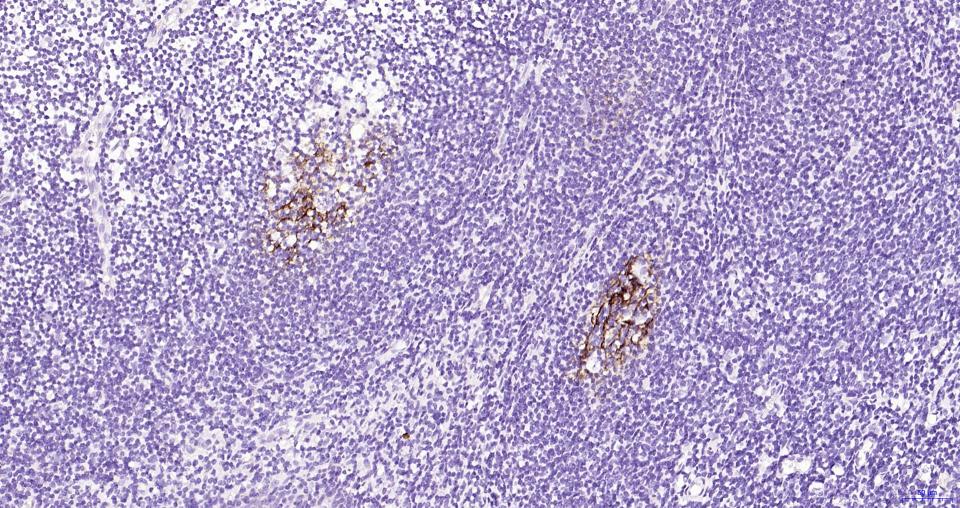

CD23是一种II型跨膜糖蛋白,是存在于B细胞表面的IgE受体。在慢性B淋巴细胞白血病(CLL)和小B细胞淋巴瘤(SLL)为阳性,套细胞淋巴瘤和小核裂淋巴细胞淋巴瘤阴性。也表达于外周血B细胞的某些亚型、B淋巴细胞和EB病毒转染的B淋巴瘤细胞系。CD23是慢性B淋巴细胞白血病,小B细胞淋巴瘤诊断和鉴别诊断有用的标记物。

The protein encoded by this gene is a B-cell specific antigen, and a low-affinity receptor for IgE. It has essential roles in B cell growth and differentiation, and the regulation of IgE production. This protein also exists as a soluble secreted form, then functioning as a potent mitogenic growth factor. Alternatively spliced transcript variants encoding different isoforms have been described for this gene.[provided by RefSeq, Jul 2011]

IHC-PHuman1:100-500

IHC-FHuman1:100-500

IFHuman1:100-500